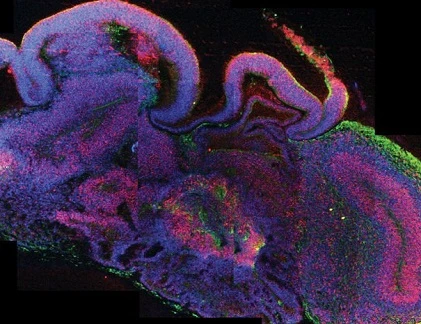

Các nhà khoa học thành công trong việc phát triển mô hình não nhỏ. Các bộ não nhỏ phát triển trong phòng thí nghiệm, được gọi là "organoids" đã được các nhà kh oa học phát triển thêm để kiểm tra thuốc và xem xét bệnh trong bối cảnh của con người. Năm 2013, các nhà nghiên cứu Áo đã phát triển các bộ não người nhỏ, với các đốm màu ba chiều có kích thước của một hạt táo. Bộ não nhỏ không có nguồn cung cấp máu, nhưng vẫn cung cấp một mô hình sinh học tốt.